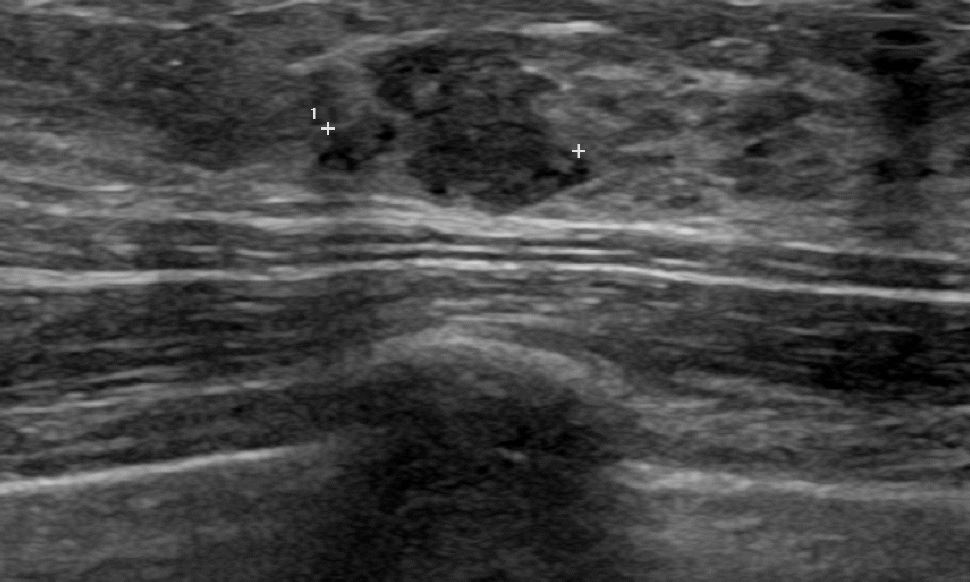

상기환자 외부검사상 이상소견으로 내원하신 40대 여성으로 우측유방의  의심스러운혹

조직검사시행해 유방암 진단되었읍니다